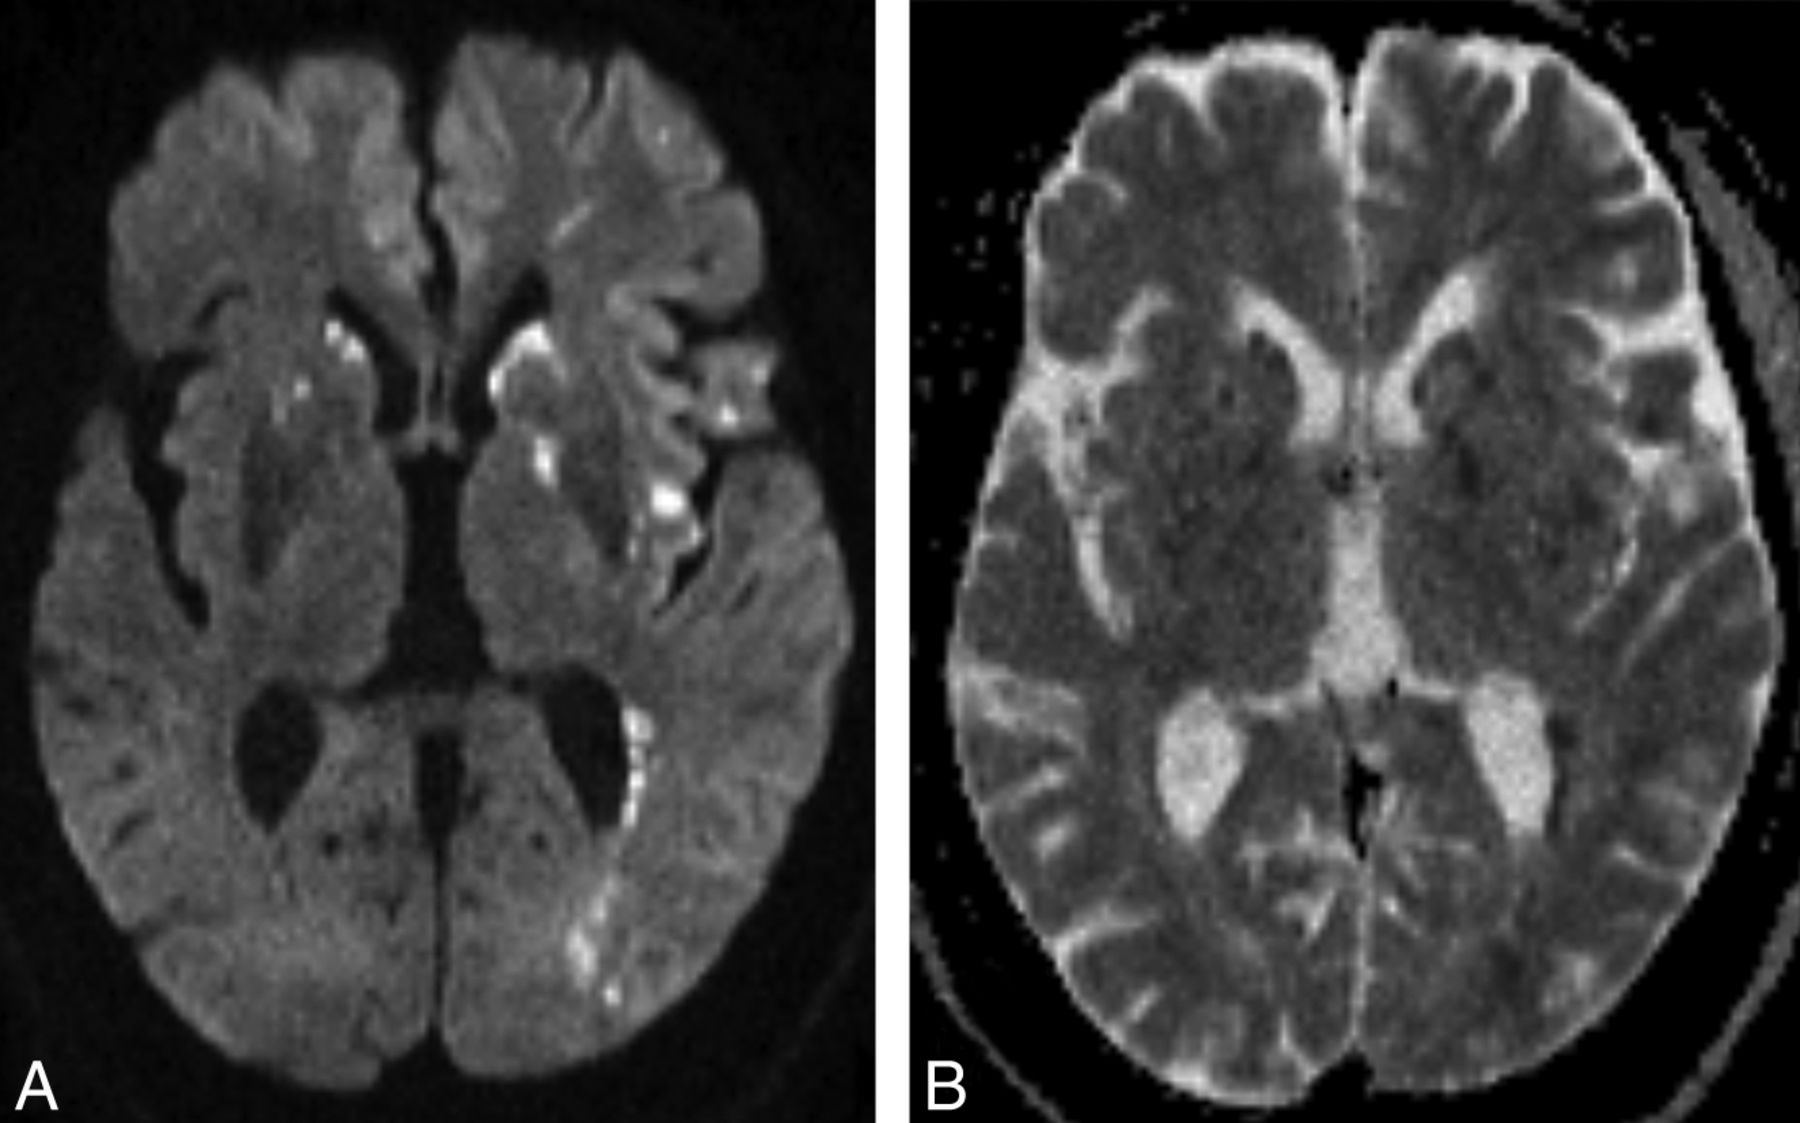

Type 1: Scattered Cytotoxic Edema

Type 1 is the most well-known pattern of CFE, which was first named the “starfield pattern” by Parizel et al in 2001.6 It is also the most common pattern in this review (61.5% of 44 MR examinations). The pattern is actually a nonspecific feature seen in all kinds of embolic events; in CFE, it tends to be reversible, with reversibility resulting in a better clinical outcome. The MR imaging findings are scattered spot lesions with restricted diffusion on DWI sequences. The signal of T2WI may be iso- or hyperintense. The lesions are distributed bilaterally in watershed zones and deep gray matter, such as the centrum semiovale, basal ganglia, and thalami (Fig 3). Of all the acute-stage MR imaging examinations, 84.6% were shown to have a type 1 pattern, while it is much less frequently seen in the subacute and late stages (18% and 0%) (Fig 2).

A 25-year-old man with a traumatic tibial bone fracture. Rapid consciousness decline was noted at postfracture day 1, and the brain MR imaging was performed at postfracture day 2. Axial DWI (A) and corresponding axial ADC image (B) demonstrate scattered spot diffusion-restricted lesions in the bilateral striatum, left posterior internal capsule, insula, operculum, and periventricular white matter (type 1 pattern).